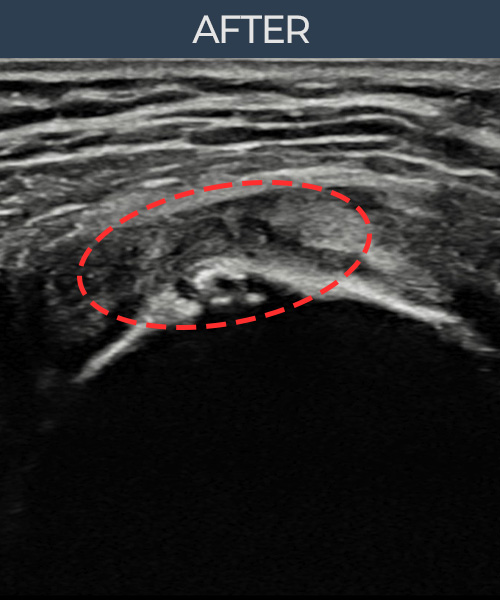

김ㅇㅇ님 · 좌측 극상근건 광범위 부분파열

좌측 어깨 광범위 파열로 수술을 권유받았으나 비수술 치료를 원해 내원하셨습니다. 초음파 검사에서 극상근건 전층에 걸친 광범위 부분파열이 확인되었으며, 어깨인대 축소봉합술 후 구조적 안정화와 기능 회복이 이루어졌습니다.